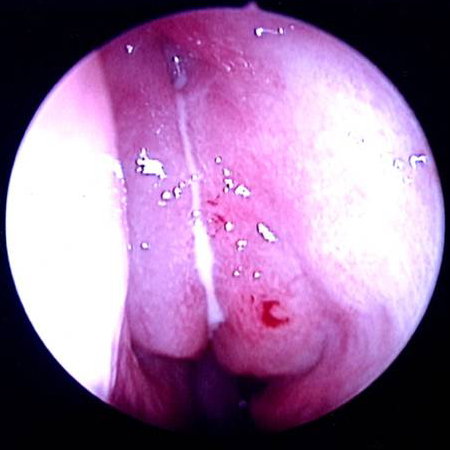

[Figure caption and citation for the preceding image starts]: Right middle turbinate and middle meatus are visible after decongestant sprayFrom the collection of Melissa Pynnonen, MD [Citation ends].

[Figure caption and citation for the preceding image starts]: Left middle meatus with severe oedema and purulent secretionsFrom the collection of Melissa Pynnonen, MD [Citation ends].

The nasal cavity should be examined for the presence of mucosal erythema or purulent discharge. Optimal examination is performed after topical decongestant spray.[18] Either an otoscope or a nasal speculum and head light may be used. However, because nasal examination may be difficult or the signs non-specific, nasal endoscopy is recommended in selected patients, including patients refractory to empirical antibiotic therapy or where there is concern for antibiotic resistance, or in immunocompromised patients.

Endoscopy can provide excellent visualisation of the nasal cavity and sinus drainage paths. There are two types of endoscope: rigid and flexible. A rigid nasal endoscope has superior resolution and only requires the use of one hand. This easily allows cultures of the nasal cavity or sinus to be obtained if necessary. A flexible nasal endoscope is more comfortable for patients, but requires both hands to use. There are flexible nasal endoscopes that have a channel for collecting cultures, but these tend to be larger and more uncomfortable and they are also more difficult to re-process. Generally, the flexible nasal endoscope is preferred in children as it is better tolerated; however, either type may be used in adults and children. Choice will depend on the practitioner's familiarity with the procedure, and most will be performed by an ear, nose, and throat specialist.